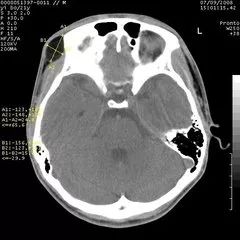

CT与普通体层摄影的区别在哪

从“计算机体层摄影”这个名词可以看出,CT实际上也是一种体层摄影,但它在成像技术上却有了突破性进展。它有了完善的扫描机架,扫描角度极大提高,轻易地实现了横断面的体层摄影。更突出的是,CT首创性地将高性能计算机技术应用到影像领域,又使用高性能的探测器同步检测X线衰减信息,影像精度空前提高,层面结构清晰,完全消除了重叠对病变遮盖的问题。更难能可贵的是,CT能调节“窗宽、窗位”等手段(后续再介绍,也可参阅我写的科普专著),使密度分辨力得到了空前的提高,原本在密度对比方面差别很小的器官组织,也可以在CT上显示出浓淡不同的清晰影像。比如,对于头颅,CT不仅能够看清颅骨的结构,而且能够看到大脑的内部结构如灰质、白质和脑室等。因此,CT极大地拓宽了X线诊断的适用范围。

CT头颅扫描图像